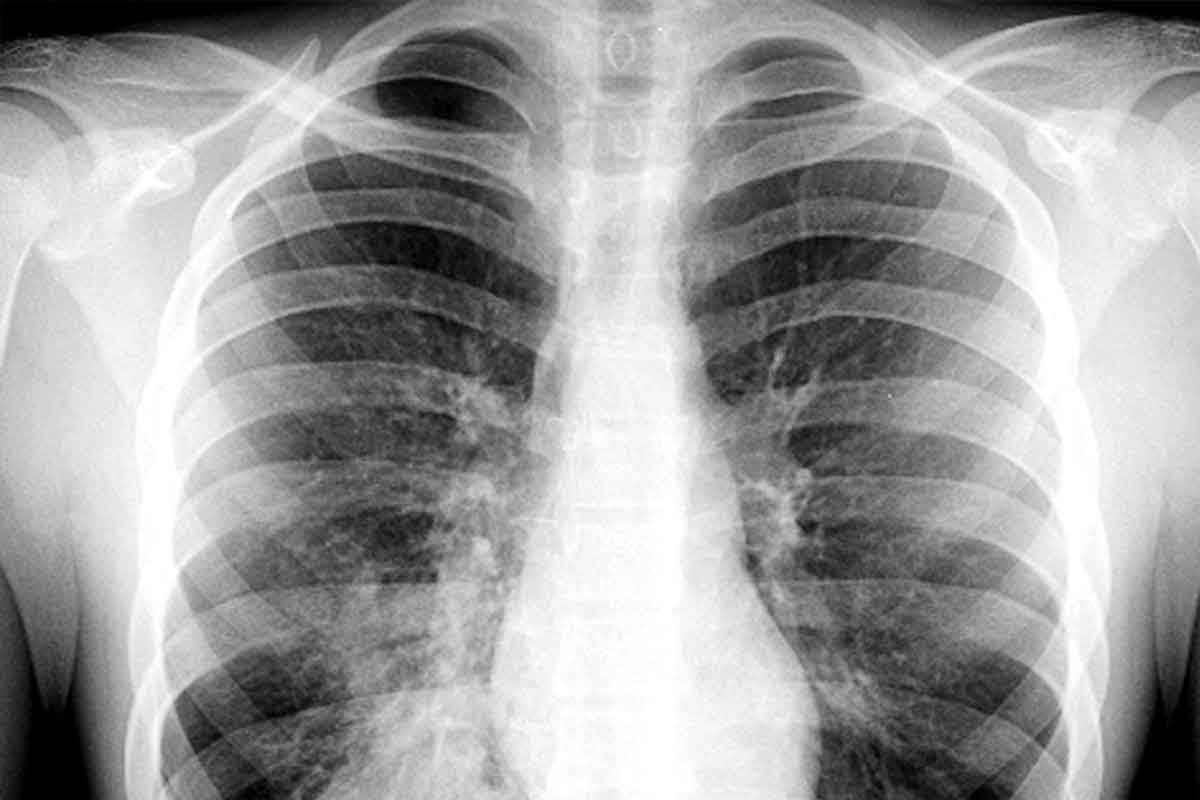

Chest congestion is a common problem that affects millions in the U.S. each year. It often comes from acute bronchitis or a chest cold. Inflamed air passages in the lungs cause symptoms like hacking cough, chest tightness, body aches, and headaches. These symptoms can really disrupt your daily life.Effective strategies detailing how to ease chest congestion and find immediate relief from cold symptoms at home.

Understanding Chest Congestion and Cold Symptoms

It’s important to know what causes chest congestion to manage cold symptoms well. Chest congestion happens when too much mucus builds up in the lungs and airways. This makes it hard to breathe and often leads to coughing.

What Causes Chest Congestion

Viral infections like the common cold or flu usually cause chest congestion. When a virus attacks the respiratory tract, it can cause inflammation and more mucus. This extra mucus gets stuck in the chest, causing congestion.